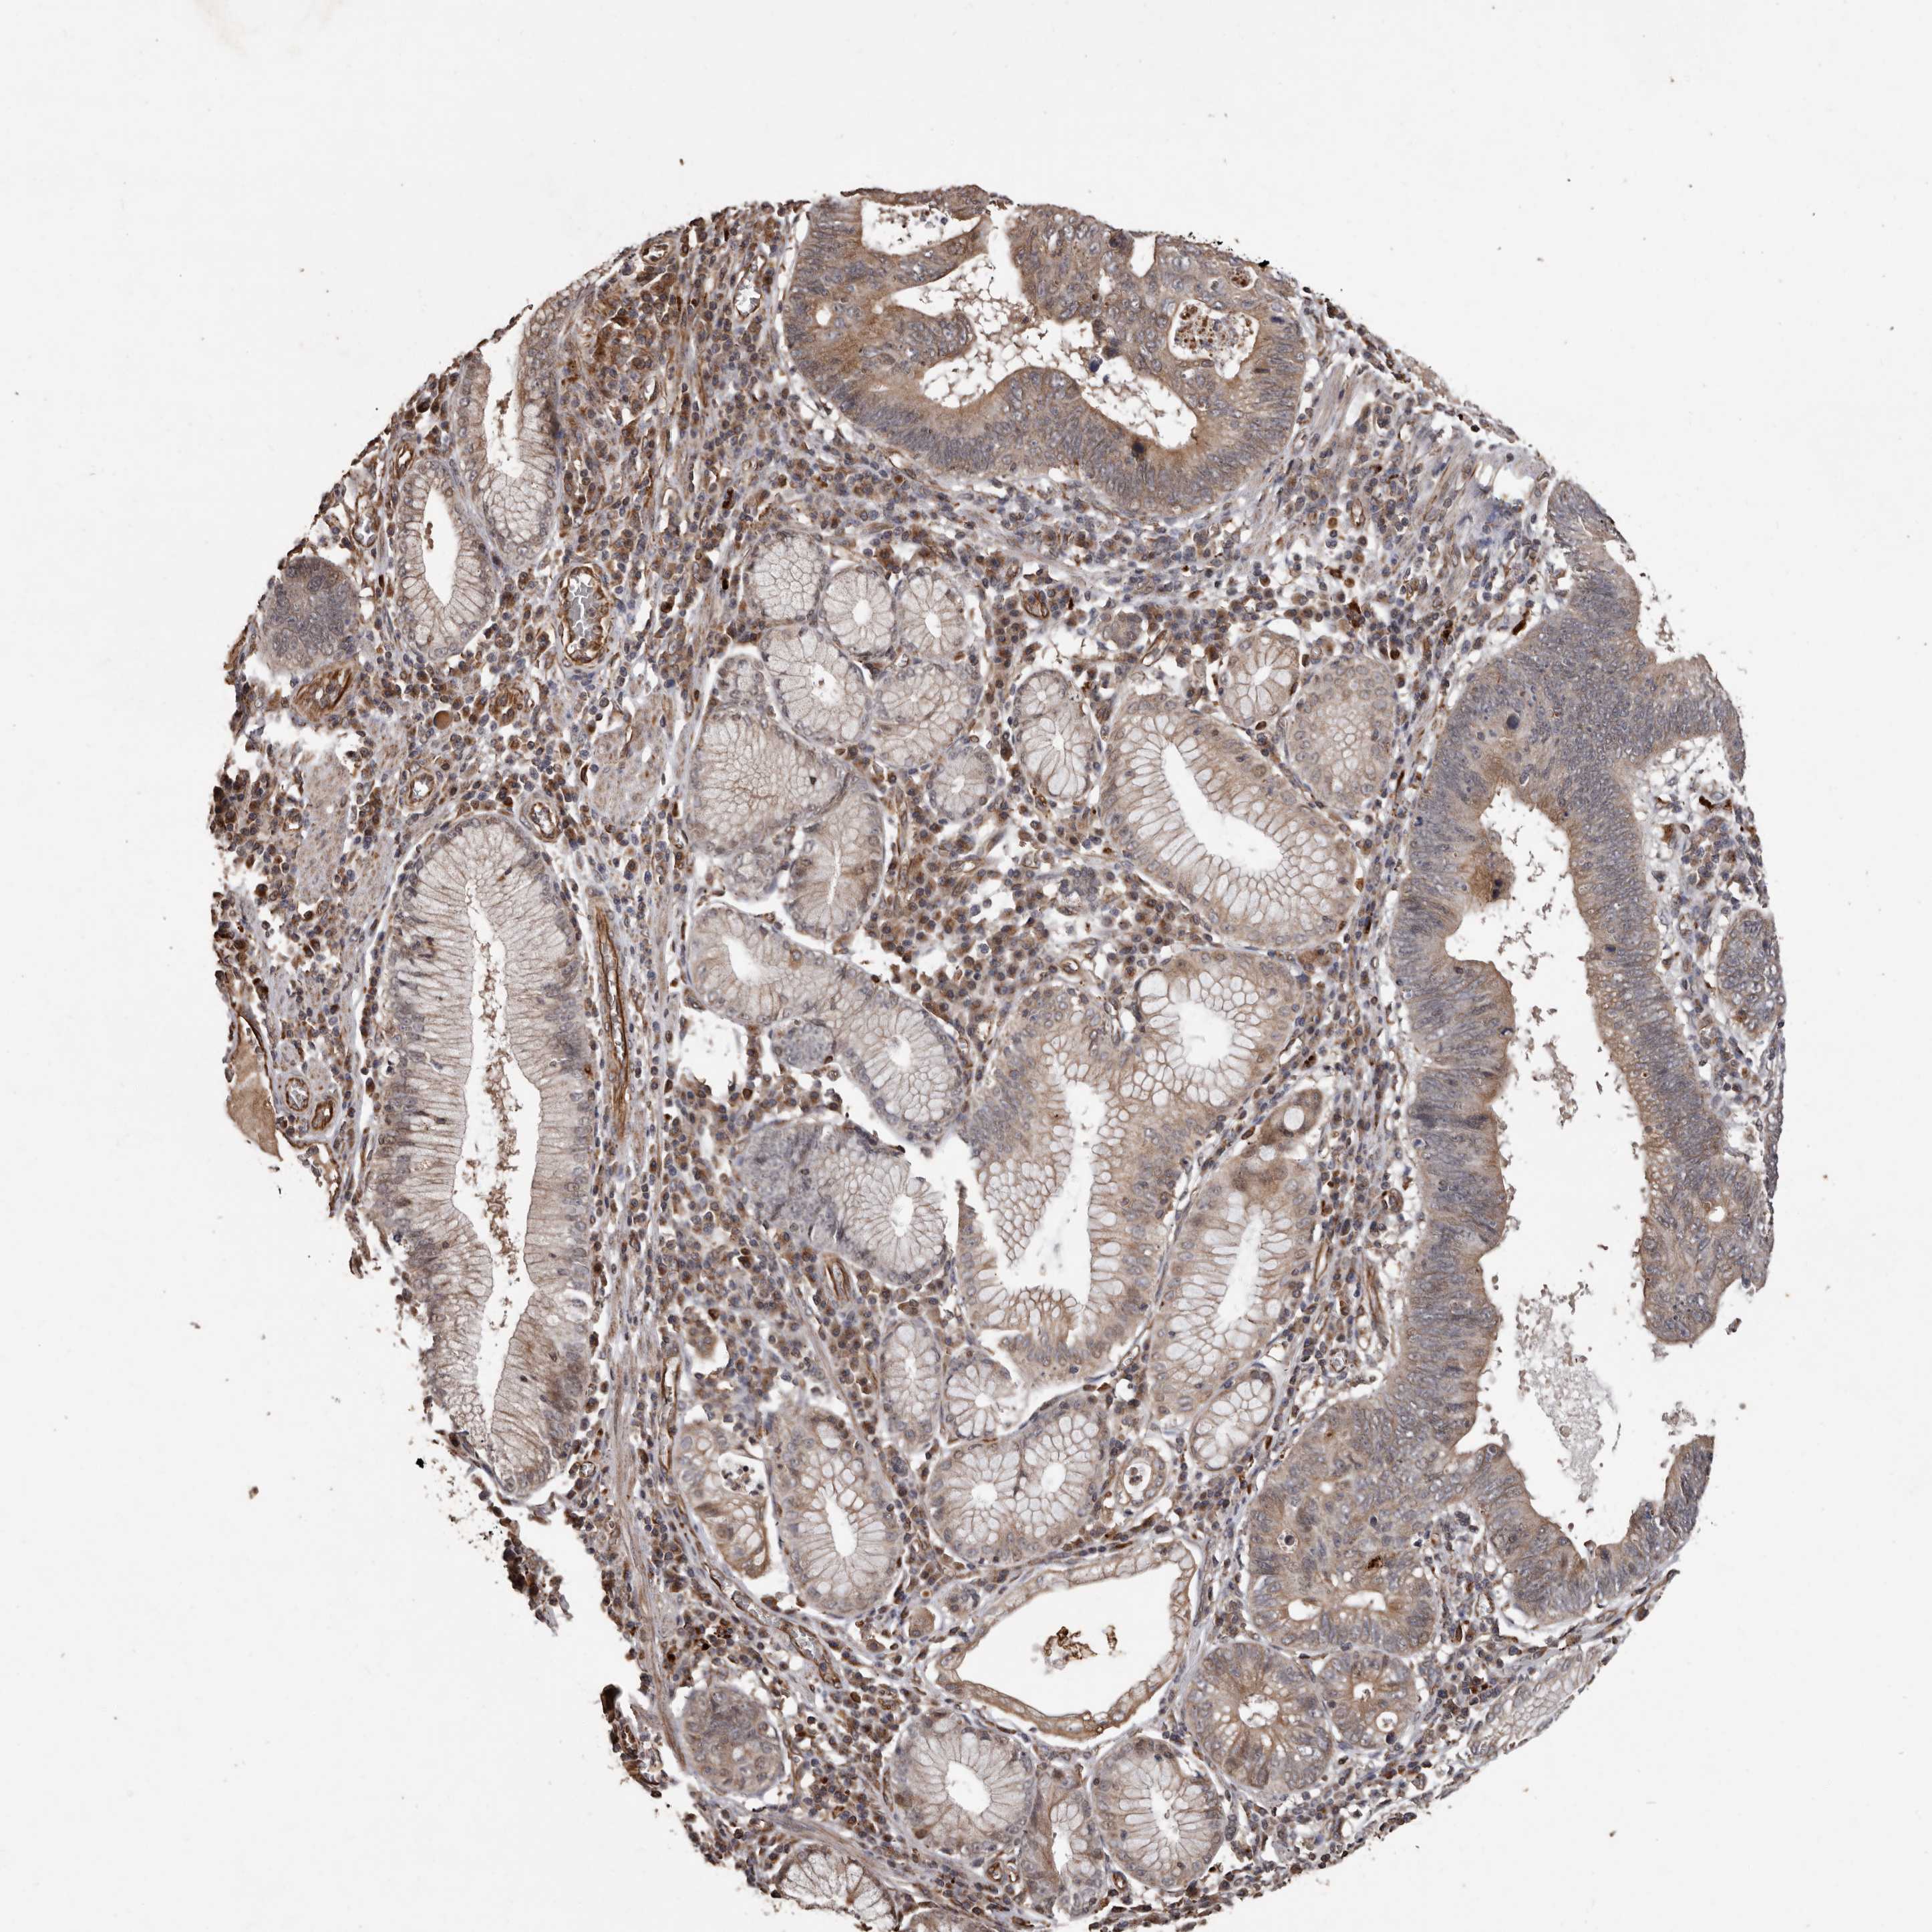

STOMACH CANCER - Protein expressioni

A mouse-over function shows sample information and annotation data. Click on an image to view it in a full screen mode. Samples can be filtered based on level of antibody staining by selecting one or several of the following categories: high, medium, low and not detected. The assay and annotation is described here.

Antibody stainingi

Antibody staining in the annotated cell types in the current human tissue is reported as not detected, low, medium, or high, based on conventional immunohistochemistry profiling in selected tissues. This score is based on the combination of the staining intensity and fraction of stained cells.

Each image is clickable and will lead to virtual microscopy that enables deeper exploration of all samples and also displays staining intensity scores, fraction scores and subcellular localization as well as patient and tissue information for each sample.

Antibody HPA029455

Staining

High

Medium

Low

Not detected

Intensity

Strong

Moderate

Weak

Negative

Quantity

>75%

75%-25%

<25%

None

Location

Nuclear

Cytoplasmic/membranous

Cytoplasmic/membranous,nuclear

Adenocarcinoma, NOS